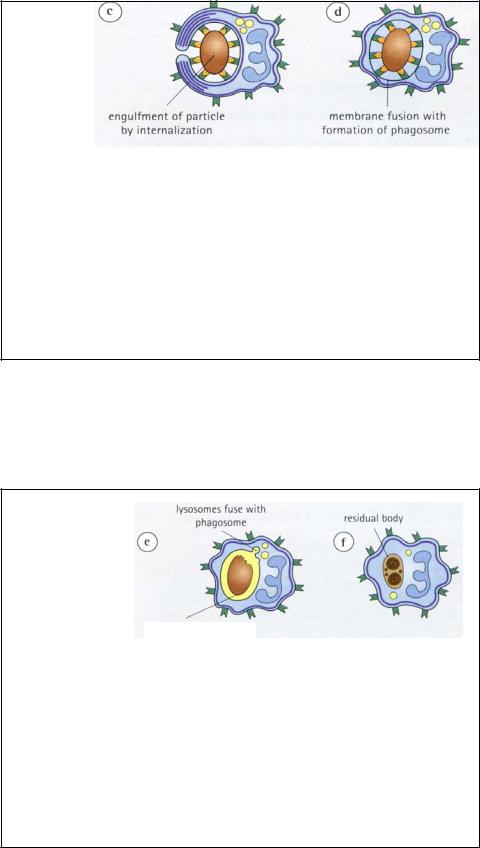

ФАГОЦИТОЗ У НЕЙТРОФИЛОВ

c)Псевдоподии сливаются, полностью окражая частицу и образуя эндоцитозный пузырек. В окончательном «склеивании» мембран принимают участия специфические белки.

d)Поглощенная частица оказывается внутри фагосомы.

71

фаголизосома

ФАГОЦИТОЗ НЕЙТРОФИЛОМ

e)Фагосома сливается с гранулами нейтрофила, особенно азурофильными, которые выделяют мощные гидролитические ферменты. Если частица бактериального происхождения, то это будет сопровождаться образованием перекиси водорода и других активных форм кислорода (супероксид-аниона) посредством ферментативных реакций восстановления кислорода.

f)Чужеродная частица разрушается с образованием остаточного

тельца. |